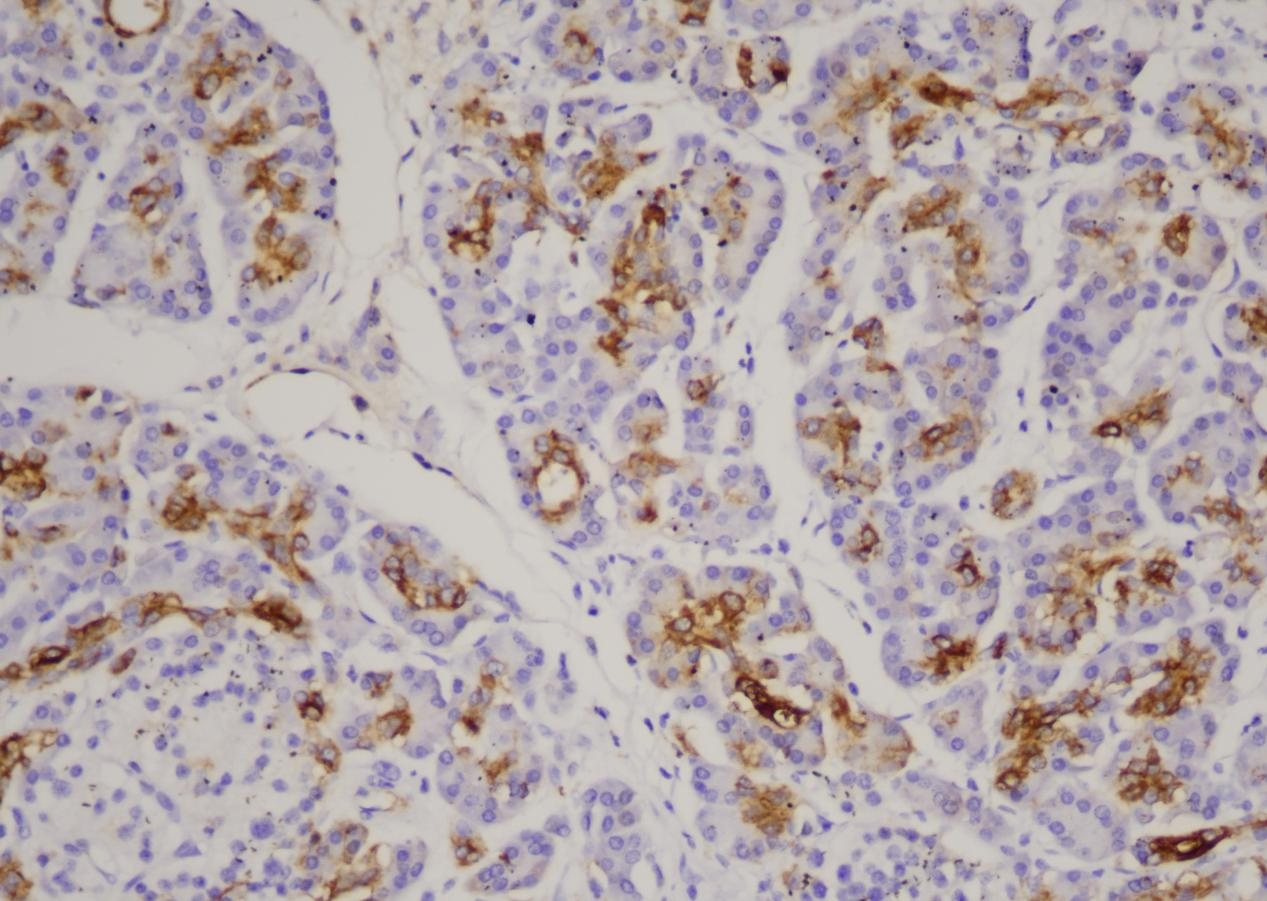

CA 19-9(Carbohydrate antigen 19-9,糖类抗原19-9)是一种肿瘤相关细胞表面糖蛋白,也称消化道癌 抗原,分子量为210kDa。在乳腺、肾、唾液腺、汗腺的导管上皮、肝胆管及导管上皮和前列腺导管上皮中表达。 CA19-9 可用于间皮瘤和腺癌的鉴别诊断、转移性腺癌的鉴别诊断。

| 细胞定位 | 细胞质/膜 |